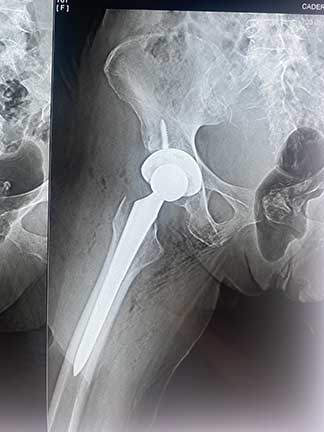

Prótesis de cadera

Es también conocida como reemplazo de cadera, la cual consiste en la sustitución de la articulación dañada o un implante de metal, cerámica o plástico que realiza la función de la articulación, mejorando el dolor.

Las indicaciones más comunes son la artrosis o desgaste de cadera en adultos mayores, otras indicaciones son las fracturas de cadera, el daño crónico o infección, artritis reumatoide, secuelas de enfermedades de la cadera o traumatismos, las cuales se presentan en adultos jóvenes y adultos mayores.

El paciente puede caminar desde el mismo día de la cirugía, se da de alta a su domicilio a las 24 horas y puede realizar actividades cotidianas en casa de forma autónoma desde la primera semana. La recuperación parte en un 80% de la función de la cadera en el primer mes, 90% de la función en el segundo mes y 92% - 98% de la función en el tercer mes.

Eliminar el dolor en la zona afectada, mejorar la función como es fuerza muscular, movimiento, estbilidad y biomecánica, logrando mejorar la calidad de vida del paciente.